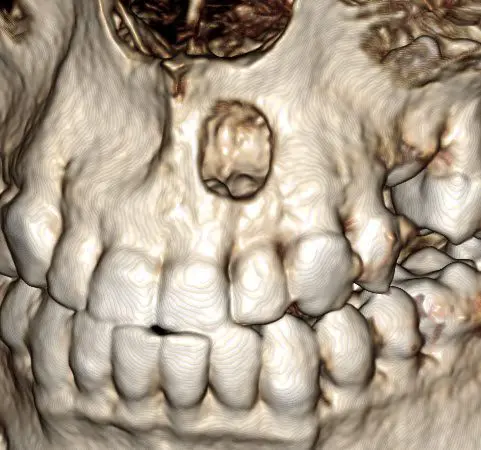

Case 3: Extra teeth. His general dentist referred this patient because his right front tooth wasn’t coming in. The 2D x-ray doesn’t look too out of the ordinary, but in the 3D view, we can see a supernumerary (extra) tooth blocking the eruption of the one we are expecting to see. We were able to refer this patient to an oral surgeon to remove the extra tooth and normalize the eruption pattern.